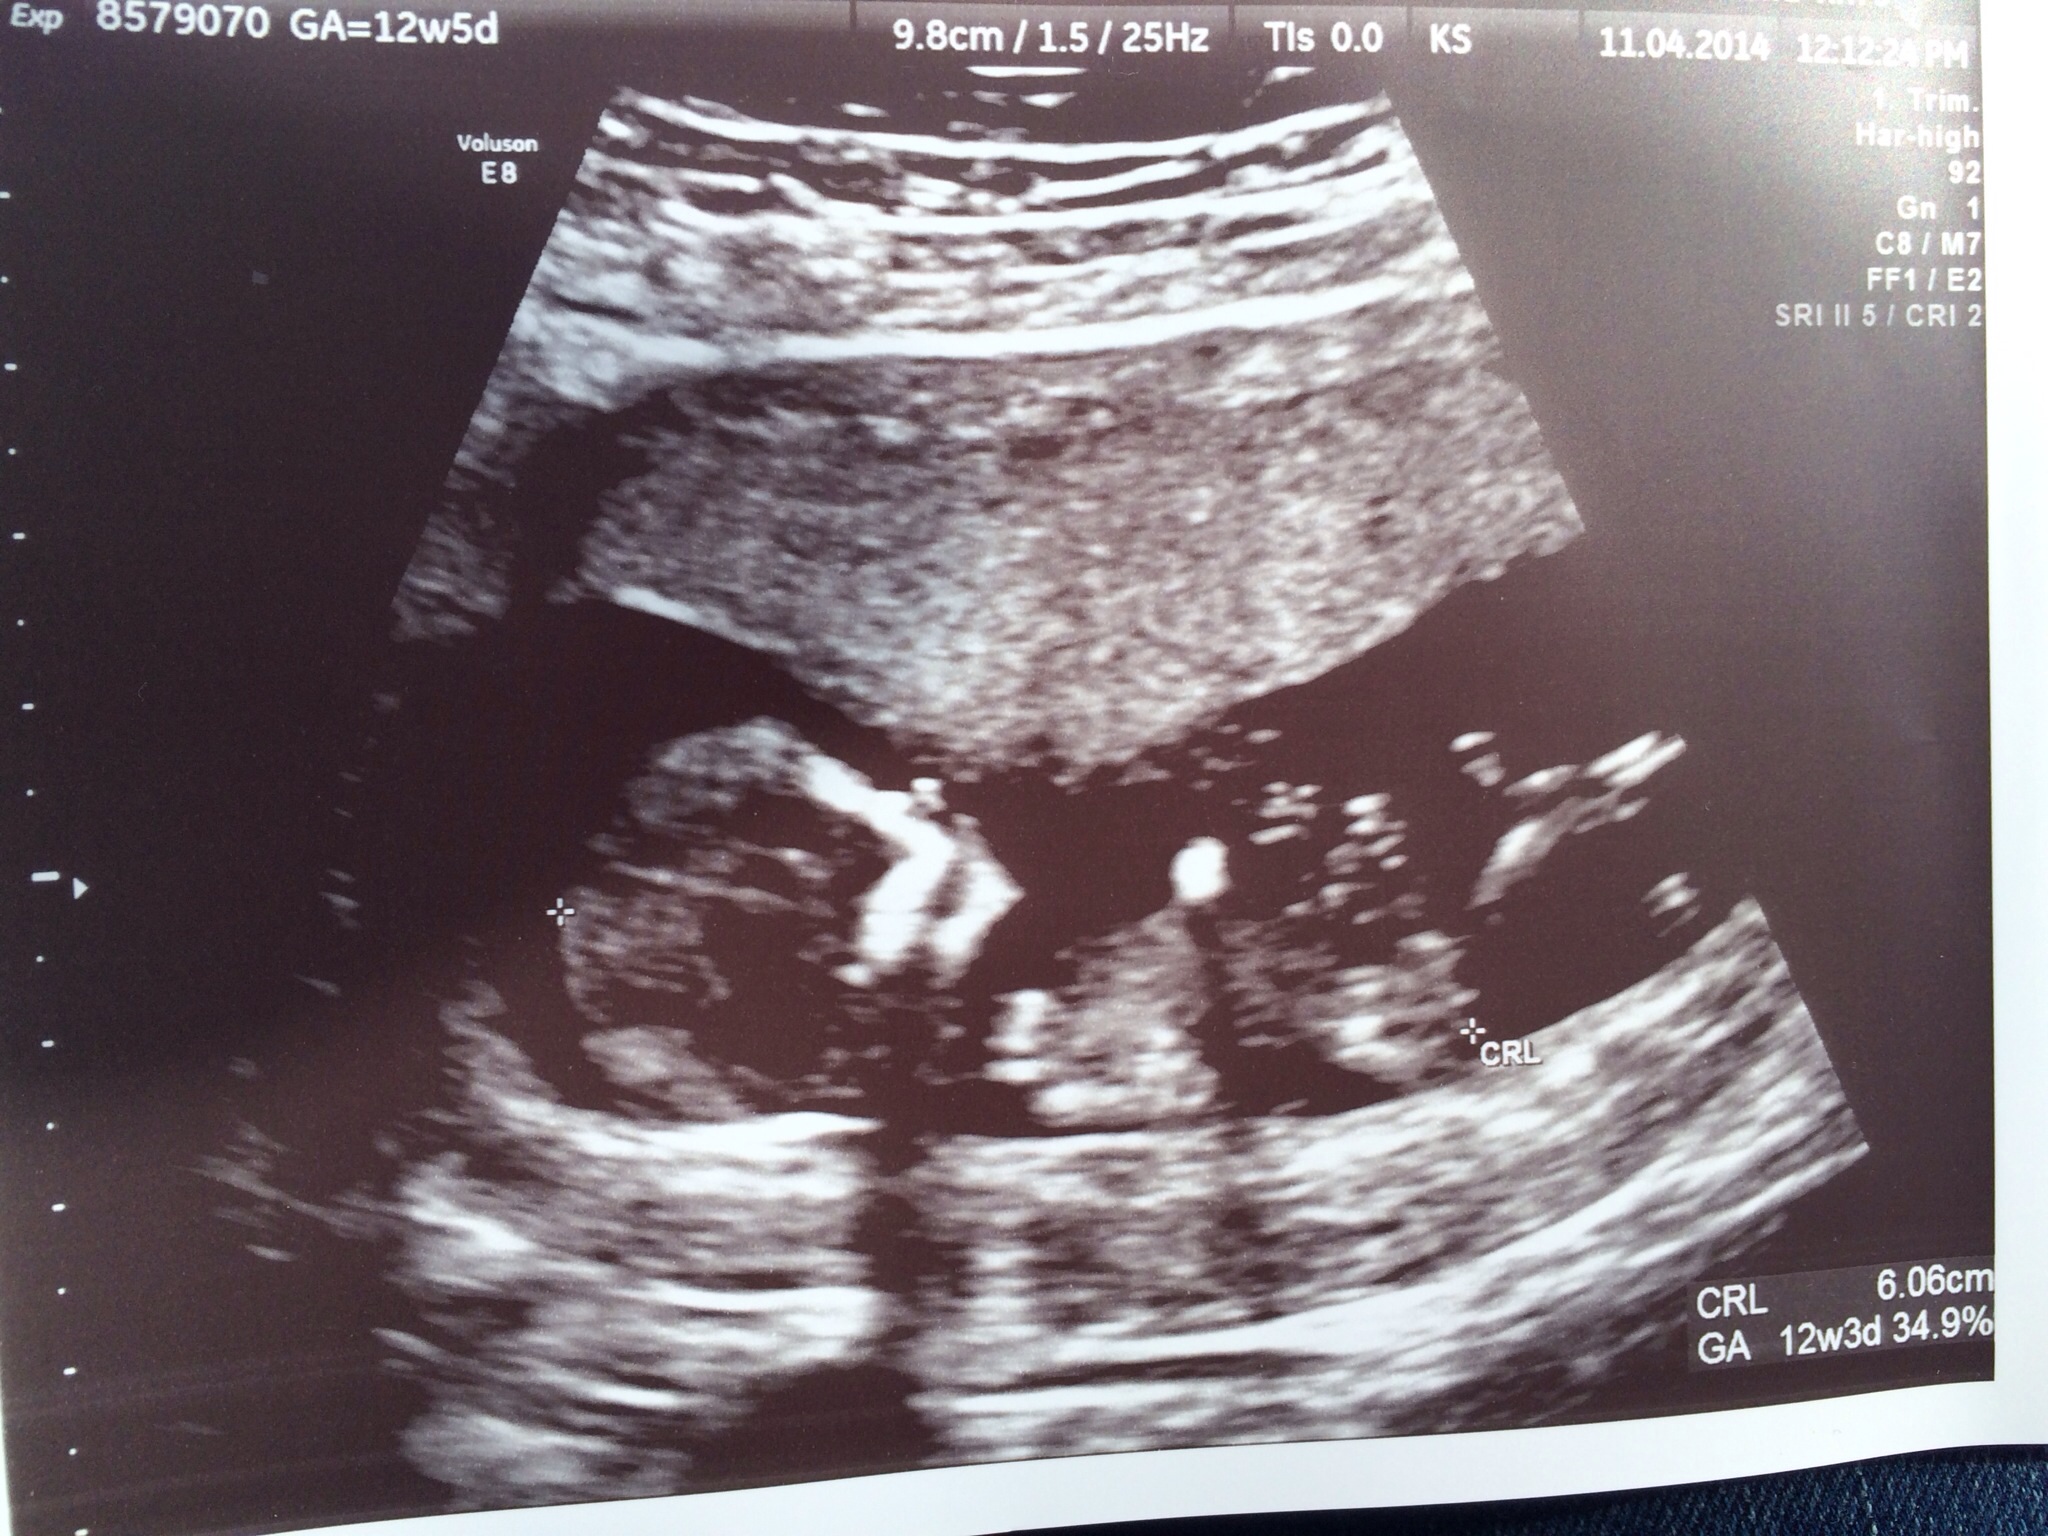

Attachment 18254

So these aren't great pics for nubs but if like to have the pics here so I can update what babe is when born:) if I can make it that long!!

All I know is I saw a totally bright parallel line and babies back was flat. Would have been a great nub shot but alas the tech took no pic!!

I was 12 weeks 5 days so not sure if that still is at the point it can rise?